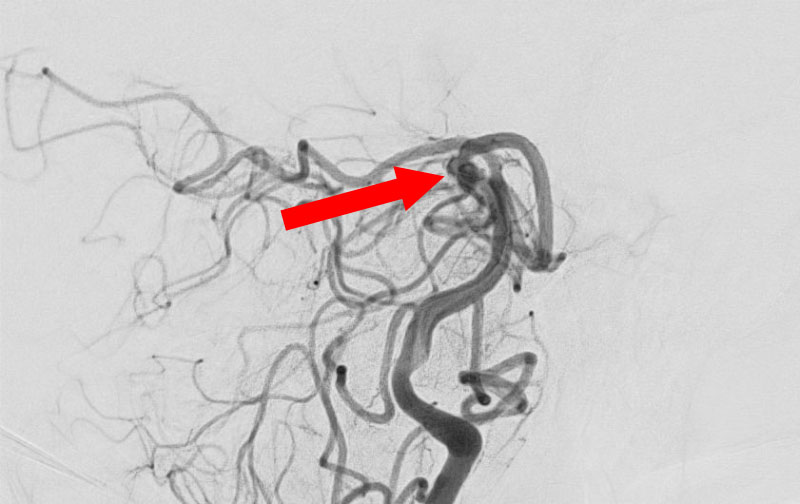

'25年11月

くも膜下出血

右内頚動脈後交通動脈

分岐部動脈瘤破裂

60代

救急外来

No.1593 手術前

No.1593 手術中

No.1593 手術後